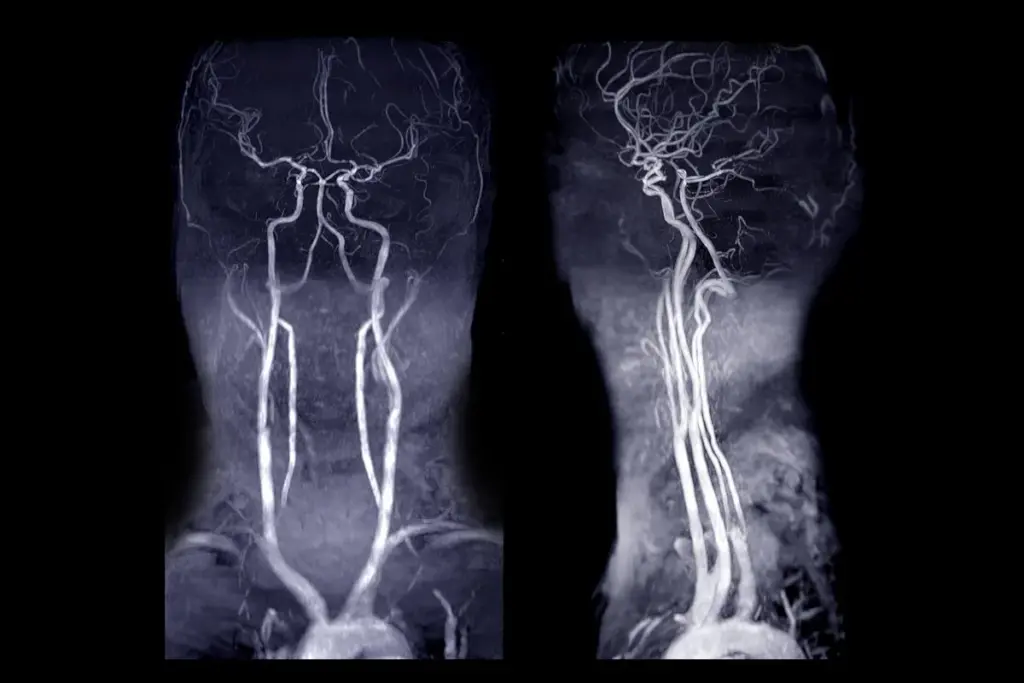

Angiography is versatile, with types like coronary, peripheral, and cerebral angiograms. It’s key in diagnosing and managing vascular diseases. Each type focuses on different blood vessels, helping in patient care.

Cerebral Angiogram

Cerebral angiography looks at brain blood vessels. It’s important for finding problems like cerebral vasospasm or aneurysms. A contrast agent is used to spot issues.

“Cerebral angiography is a top tool for brain disease diagnosis and treatment,” a neurology journal states. It helps doctors plan treatments like embolization or surgery.

Imaging Techniques

Modern angiography uses advanced imaging to see inside blood vessels. Digital subtraction angiography (DSA) is one method. It improves image quality by subtracting images before and after contrast agent injection.

We use these technologies to get clear, detailed images. These images help us make accurate diagnoses.

Other imaging techniques include X-ray, magnetic resonance angiography (MRA), and computed tomography angiography (CTA). Each method has its own benefits. We choose the best one based on the patient’s condition and the area being examined.